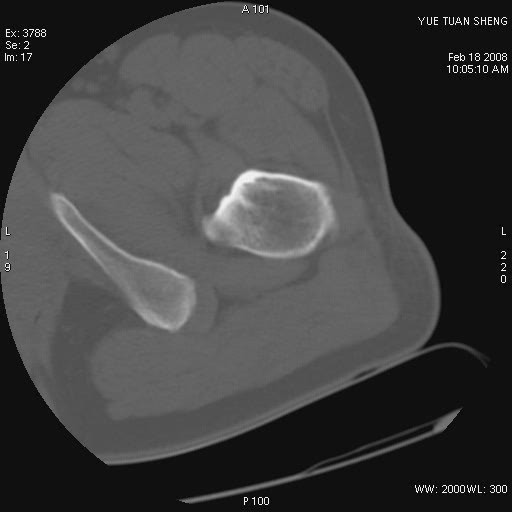

患者,男,56岁,左髋部疼痛1个月,x线:左股骨头高密度影,性质待定,右侧正常。左髋ct如图

左股骨颈区椭圆形磨玻璃样影,边缘明显硬化环环绕,其内见斑点状类钙化高密度影考虑 良性骨病-----骨纤,骨化性纤维瘤,内生软骨瘤。